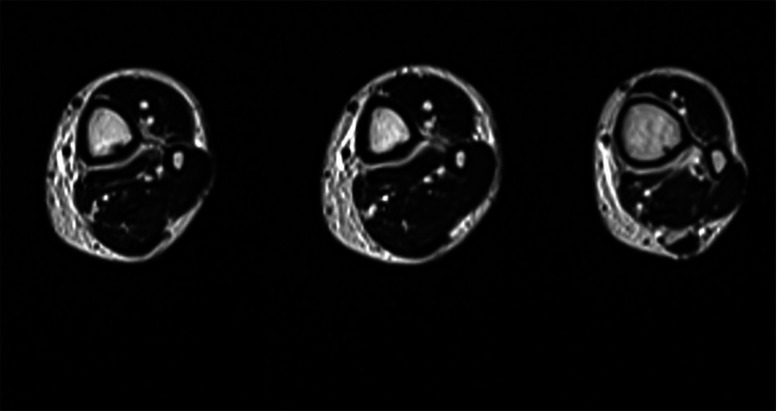

MRI of the left leg (Fig. 1, Fig. 2, Fig. 3) showed bone marrow edema extending from the middle to the distal third of the tibial diaphysis. In the posterior middle-third of the tibial diaphysis, serpiginous subcortical images with oblique course and flow-voids on T1- and T2-weighted were seen. Similar findings were visible at the distal third of the tibial diaphysis. These findings were consistent with dilated vessels connected to anomalous venous structures with an intra-osseous course. At the cortical entry point of the distal third of the tibial diaphysis, periosteal reaction on the posterior side was visible. These intraosseous venous structures were connected to deep venous branches at the middle third of tibia. Small superficial varicose veins were also visible at the medial side of the leg. Subcutaneous edema was present.

Fig. 3.

Magnetic resonance axial T2-weighted images showing a serpiginous structure entering the bone from a cortical entry point at the distal third of the tibial shaft.